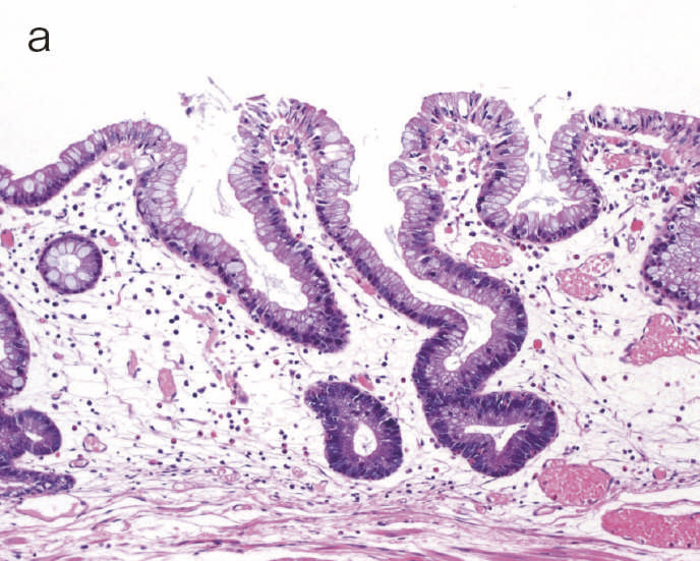

図9 Dysplasiaの代表的な組織像

- LGDの組織像(HE染色):異型腺管では表層への分化傾向が見られる。

- aのp53免疫染色:異型腺管深部側優位にp53蛋白過剰発現が見られる。

図11 LGDと散発性腺腫の代表的な病理組織像と特徴的免疫染色像

表層への分化傾向を示すLGDでは異型腺管深部側優位にp53蛋白過剰発現が見られるのに対し,散発性腺腫ではp53蛋白異常発現は認められない。また,Ki-67(増殖マーカー)染色においては,LGDでは細胞増殖帯が粘膜深層~中層に位置するが(bottom-up pattern),散発性腺腫では細胞増殖帯が腺管表層~中層に分布する(top-down pattern)(CQ 12,CQ 13)。